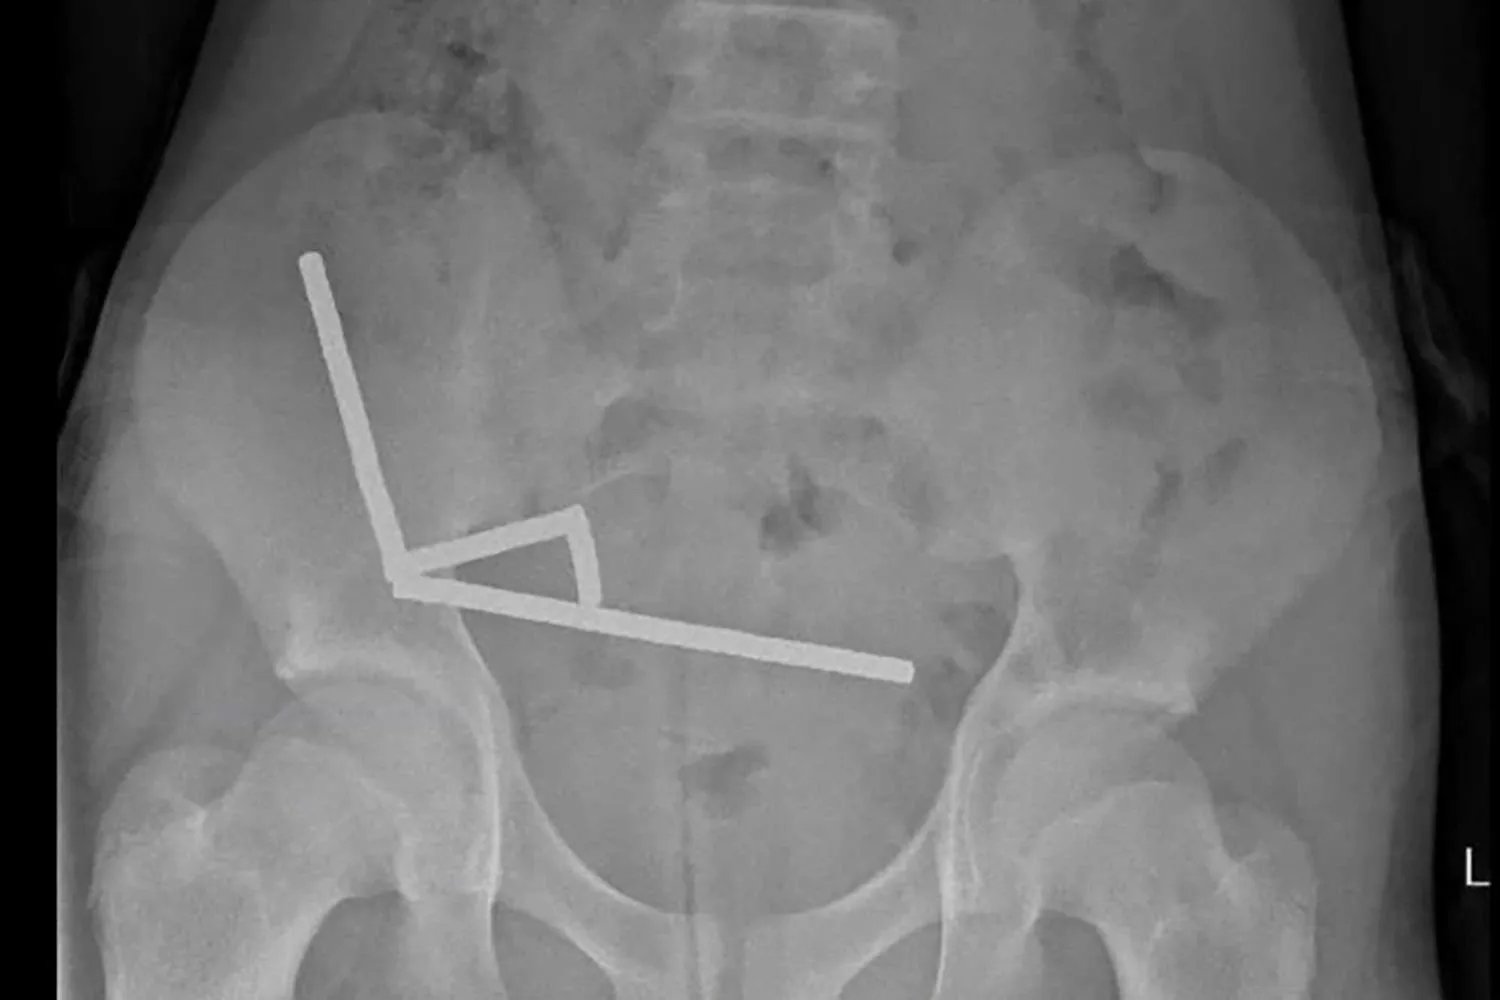

Researchers said an X-ray was taken and showed “four linear chains of magnets” linked together, composed of what the boy indicated was “approximately 80–100 5x2mm high-power (neodymium) magnets” that he allegedly purchased from online retailer Temu.

Photos published in the study showed the retrieval process, and indicated that the magnets “appeared to be in separate parts of bowel” but were “adhered together due to magnetic forces.”